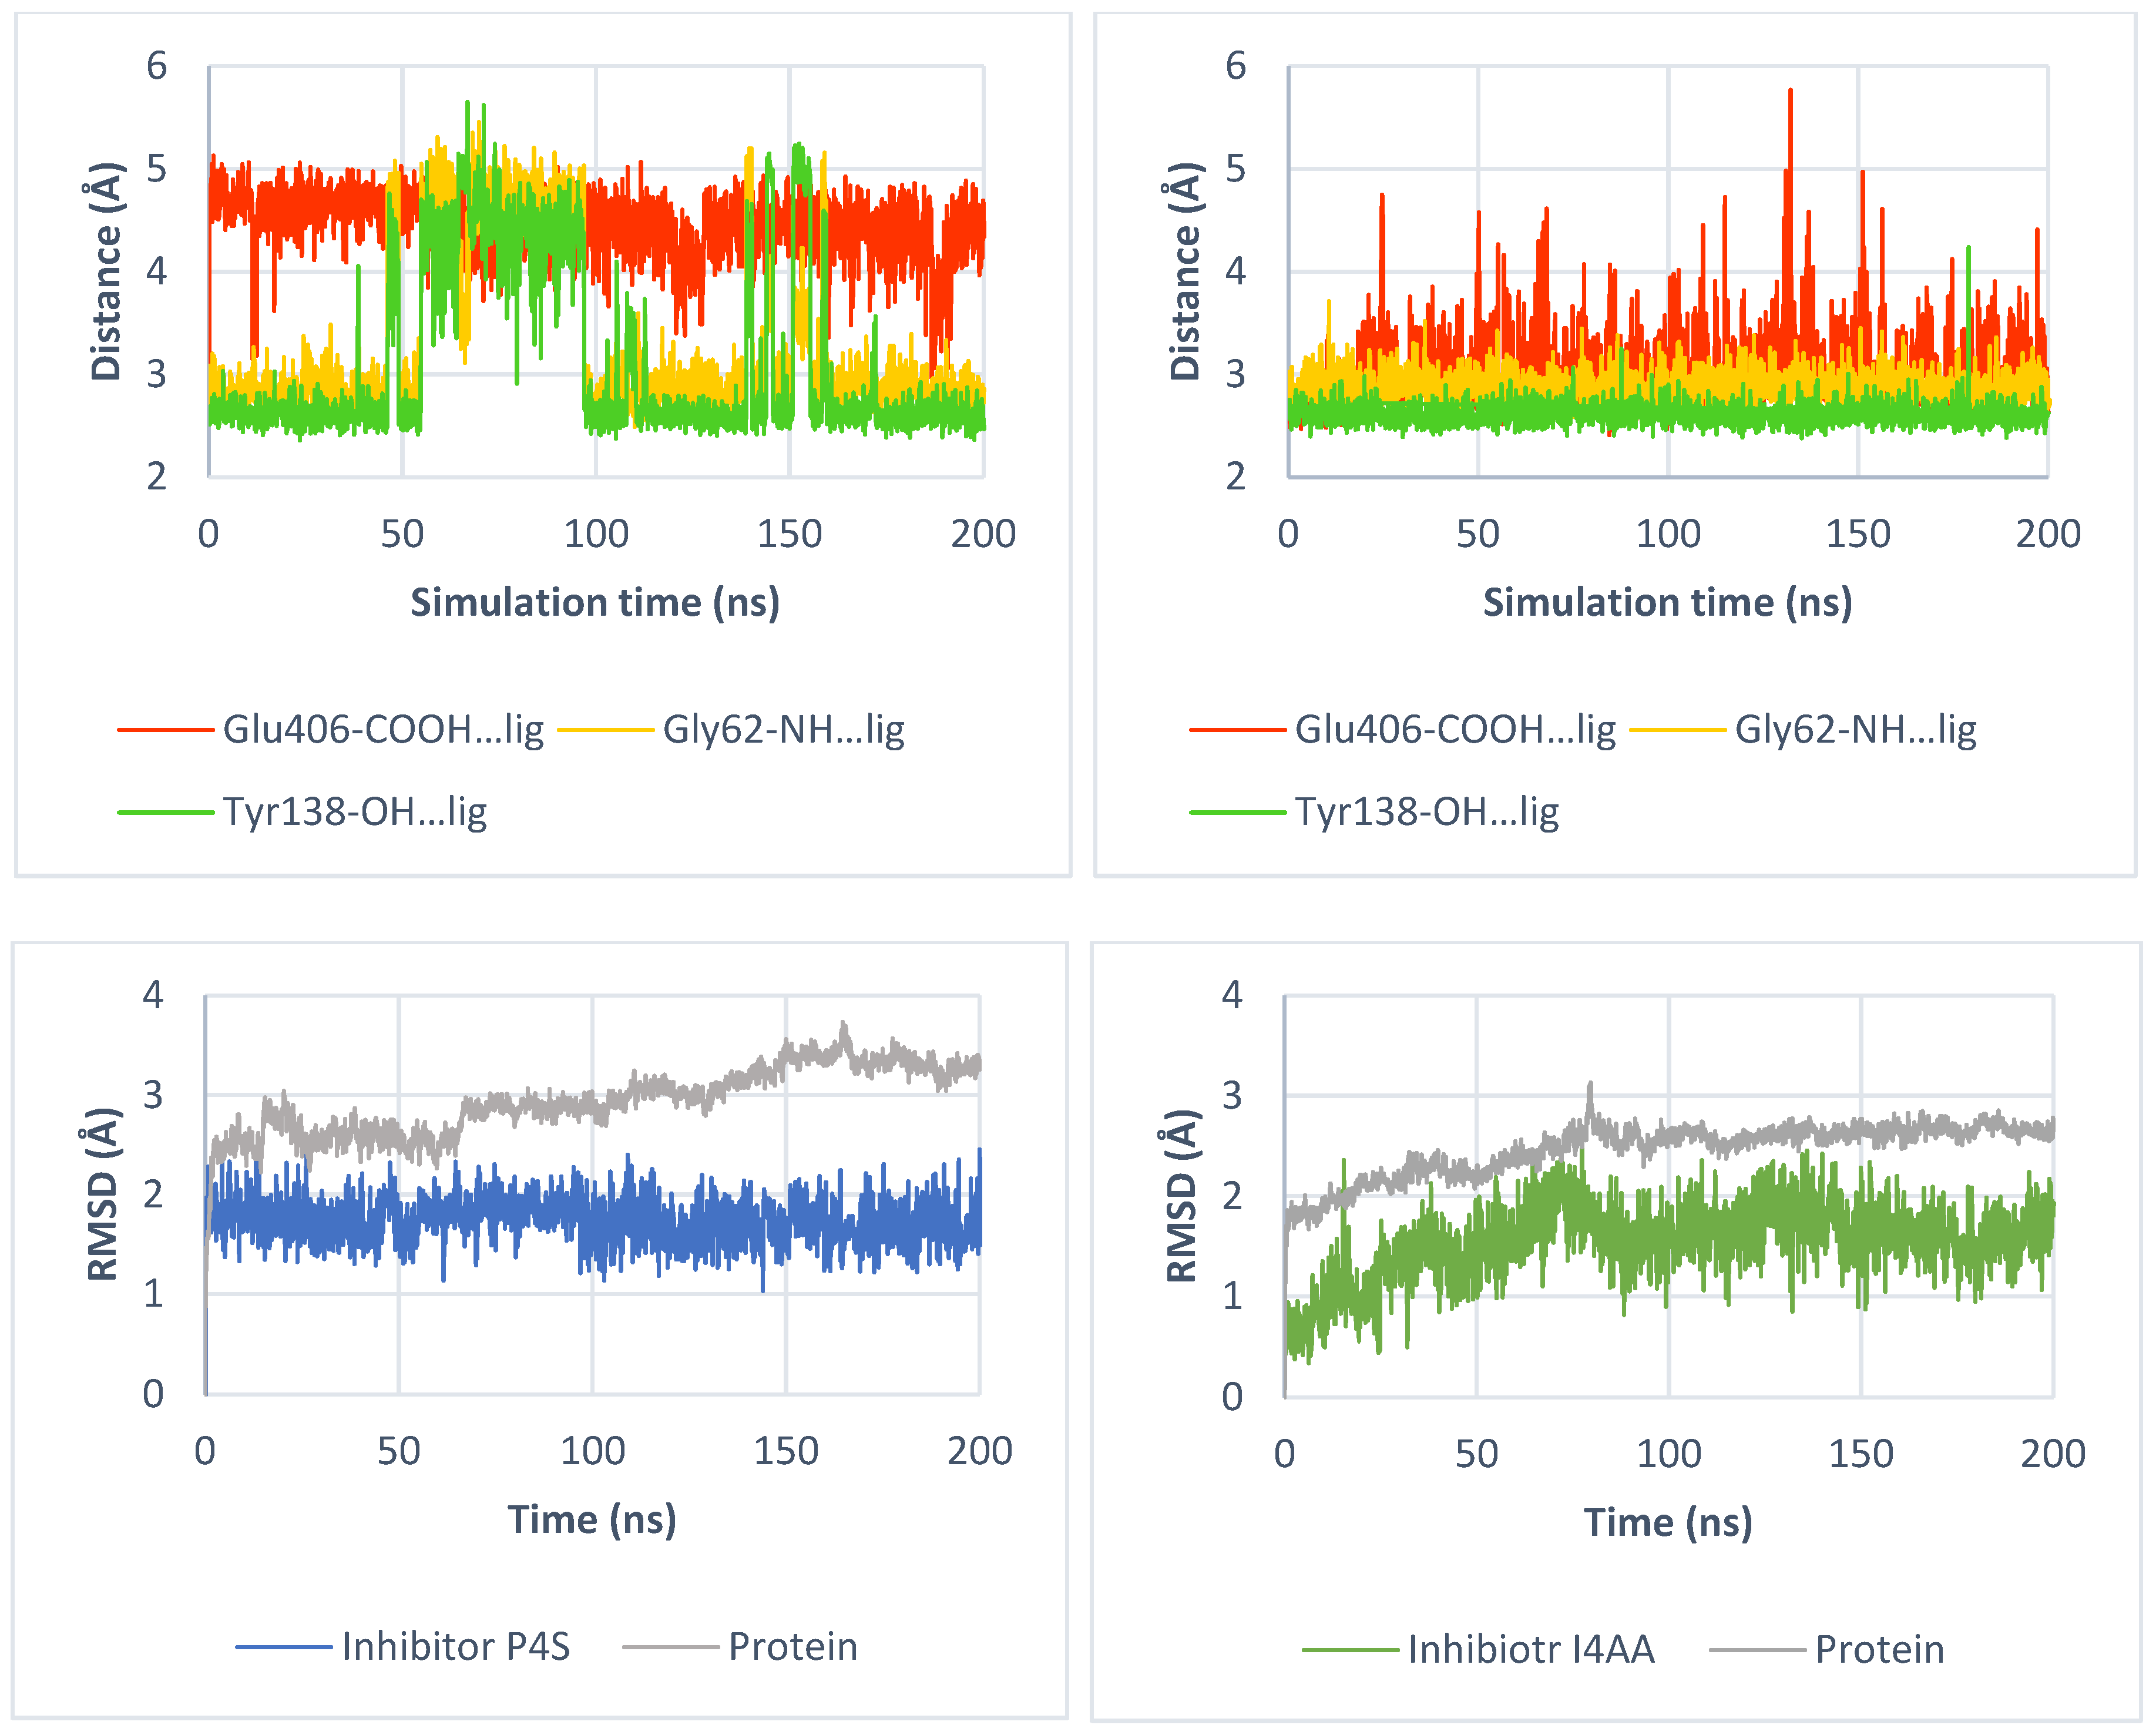

2.3.2. Binding of Taurine Transporter Inhibitors

2.4. Role of Mutations in Taurine Transporter

2.4.1. Glu406 Is Crucial for SLC6A6 Transporter Activity